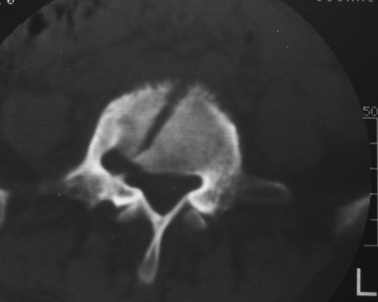

以下是引用dyqct在2007-3-1 18:04:00的发言:[br]腰5、骶1呈溶冰状骨质破坏,边界清楚,无明显硬化,内见多数沙粒状死骨,周围软组织肿胀。[br]考虑:腰5、骶1结核,建议严格抗结核治疗后复查。

以下是引用gaoxiao在2007-3-1 18:02:00的发言:[br]腰5骶1椎体见骨质破坏,其内见死骨形成,椎前软组织肿胀,感染性病变,腰骶椎tb。

以下是引用gaozhengyi在2007-3-1 19:39:00的发言:[br]骨质破坏并砂砾样死骨为椎体结核的表现。椎体结核骨质破坏区的特点是呈虫蚀状,常可见硬化缘。死骨表现为片状高密度影,正如本例。